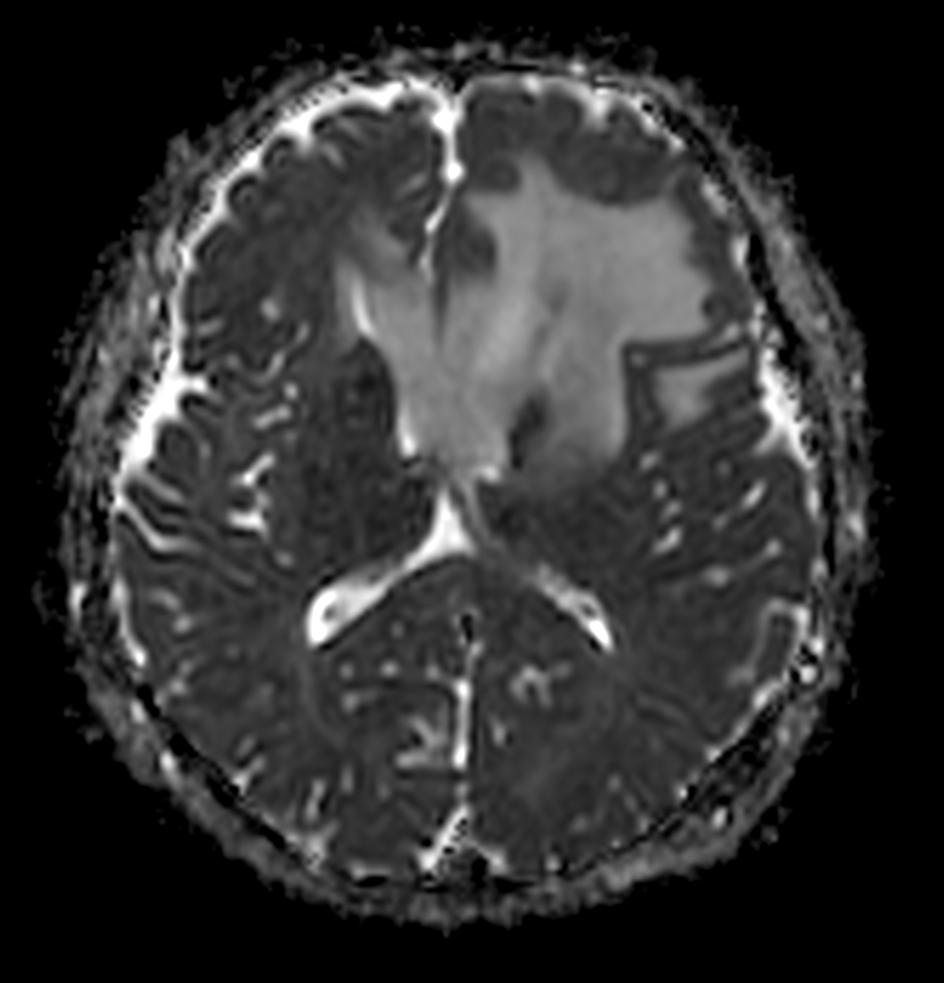

DWI (eADC)